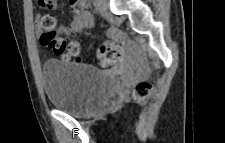

Мультиспиральная КТ мочевого пузыря является частью протокола обследования органов малого таза. Это высокоинформативный рентгенологический метод исследования, позволяющий детально визуализировать мочевой пузырь, нижнюю часть мочеточников, внутренние половые органы, прямую кишку.

Зачастую подобное исследование проводится при мочекаменной болезни (МКБ) для выявления конкрементов, определения их положения, размеров и плотности. Локализация конкремента существенно влияет на терапевтическое лечение МКБ, а наличие дивертикулов стенки мочевого пузыря на возможность самостоятельного выхода камня.

Также при данном исследовании возможно выявить утолщение стенки мочевого пузыря, что при диффузных изменениях может соответствовать проявлениям цистита, а локальные или неравномерные утолщения – характеризовать патологический процесс обусловленный новообразованиями.

Что позволяет увидеть КТ мочевого пузыря

- цистит;

- дивертикулы мочевого пузыря

- цистоцеле

- уретероцеле

- варианты строения мочеточников

- камни мочевого пузыря;

- травмы, разрывы и растяжения органа;

- опухолевые новообразования.